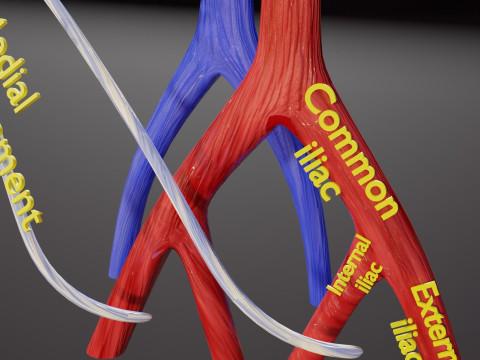

The model meshes include adult circulation versus circulation in Tetralogy of Fallot (TAF), arrow labels and text labels. The blood flow in a patient with Tetralogy of Fallot is outlined in this model. To contrast it to normal blood circulation a separate model of normal circulation is included. The Tetralogy of Fallot (OVER RIDING OF AORTA, PUL STENOSIS, VENTRICULAR SEPTAL DEFECT, RIGHT VENTRICULAR HYPERTROPHY), fossa, ligament teres , venosus, and arteriosus are duly depicted with proper labelling and blood flow directional arrows. Excellent model for teaching, demonstration and knowlegde of human body. The models include both procedural and image textures blend files separately. The texture file include diffuse, roughness and normal png and jpeg based on non overlapping UV maps.